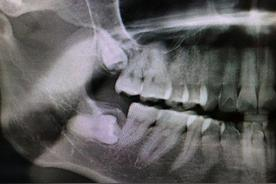

那为什么医生会说她的智齿需要拔呢?一看片子,好家伙,这四颗牙齿虽说茁壮成长,但也确实是在各长各的,难怪医生说要拔。

智齿阻生

如果只是长的不太整齐,但不影响其他牙齿,我们或许可以忍受,但我朋友有一颗尽头牙是横着长的,医生说这叫阻生,阻生牙的力量很大,会推着其他牙齿往前挤,难怪她觉得读书时候牙齿挺齐的,年纪越大牙齿却越来越不整齐,那可能就是尽头牙在“作怪”。

她的情况还比较严重,尽头牙抵着前面一颗牙齿的牙根和牙冠,医生告诉她,一天两天没感觉,但等到牙齿会疼的时候,问题就大了,到时候就两颗牙都保不住。

“同归于尽”的两颗牙